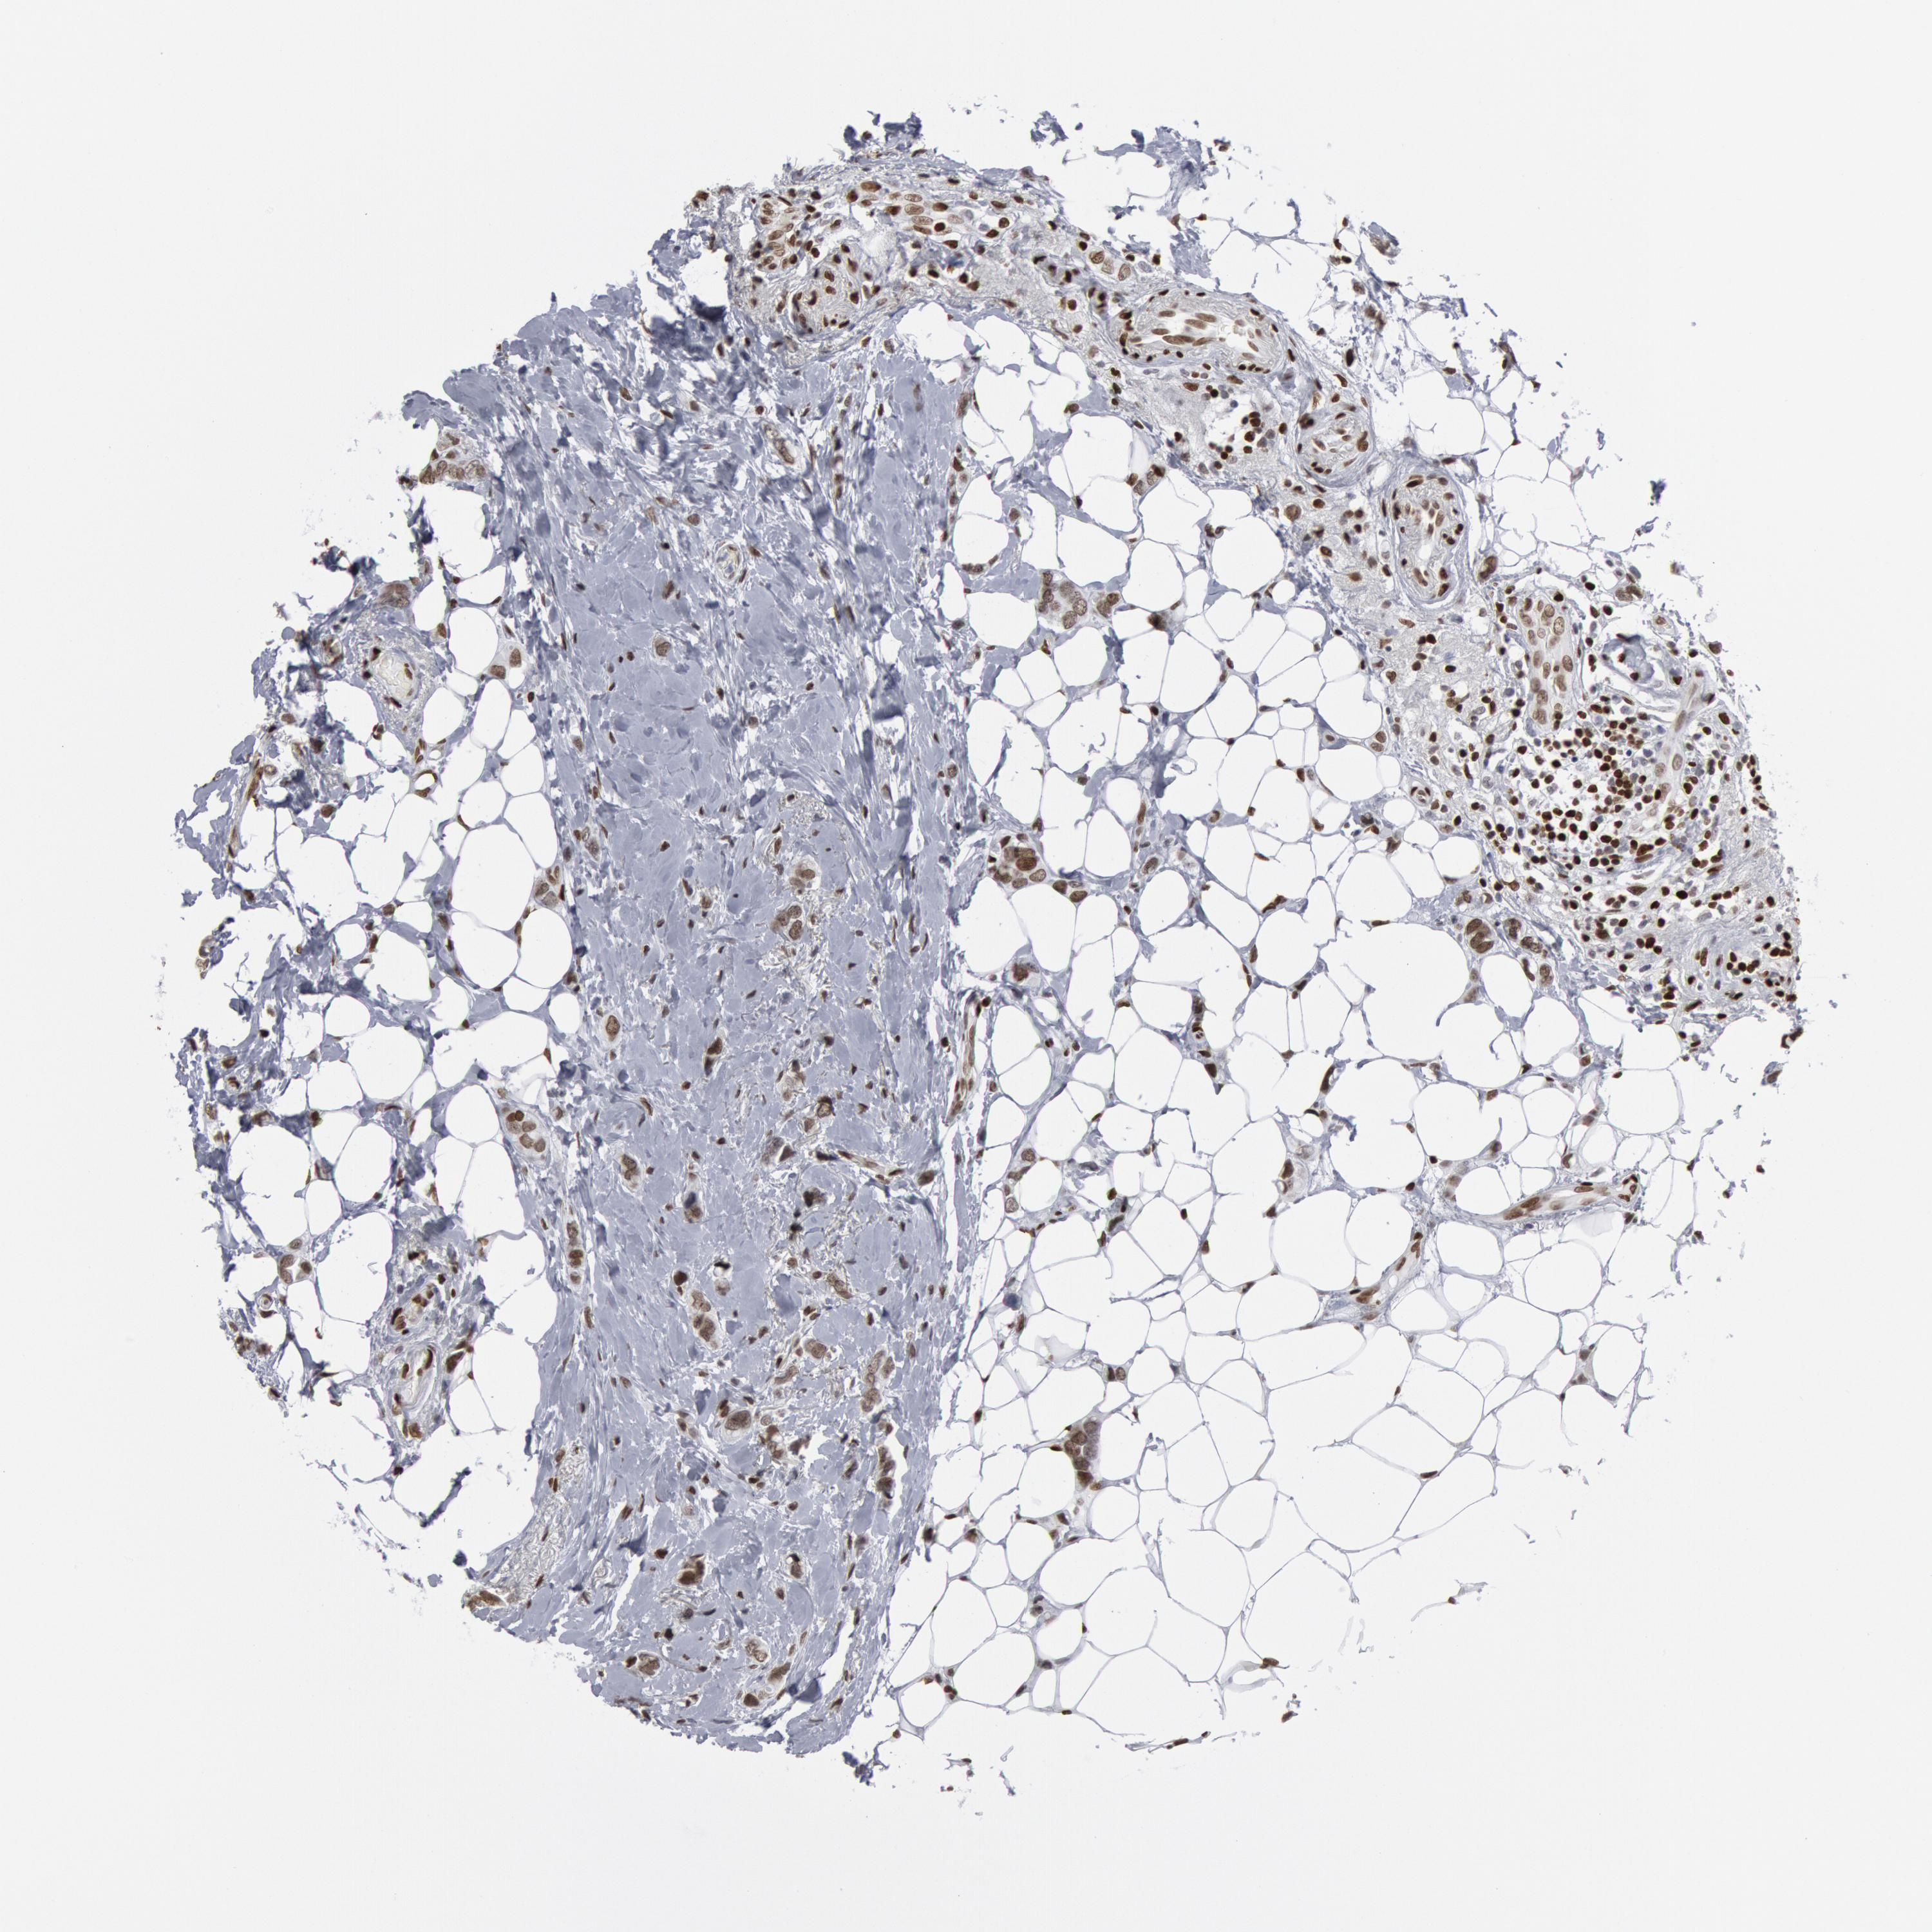

CANCER BREAST CANCER Show tissue menu

BRCA TCGA BRCA VALIDATION PROTEIN EXPRESSION